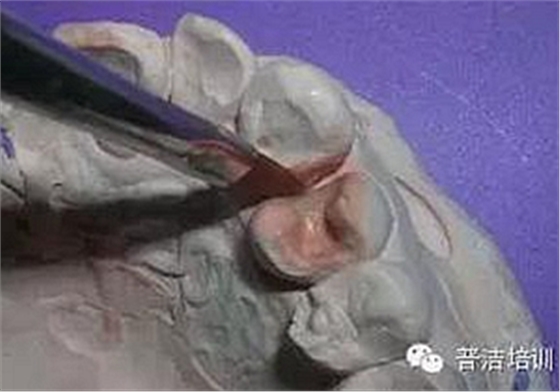

左上4近中鄰 牙合 面齲,3 4之間與對頜牙的牙尖形成咬牙合接觸。從3的磨耗程度可以看出4的近中牙合面受力也很大,單純充填可能不長久。決定用金屬嵌體修復(fù),但患者對美觀比較在意,瓷又有點(diǎn)貴,最后選擇樹脂嵌體

釉質(zhì)鑿制備“明尼蘇達(dá)溝”,增加固位

鄰面預(yù)備到自潔區(qū),齦壁盡量在齦上,齦壁下方距鄰牙之間要有0.6MM左右的間隙,以保證硅橡膠強(qiáng)度,因樹脂強(qiáng)度稍差,峽部預(yù)備比金屬要稍寬一點(diǎn)